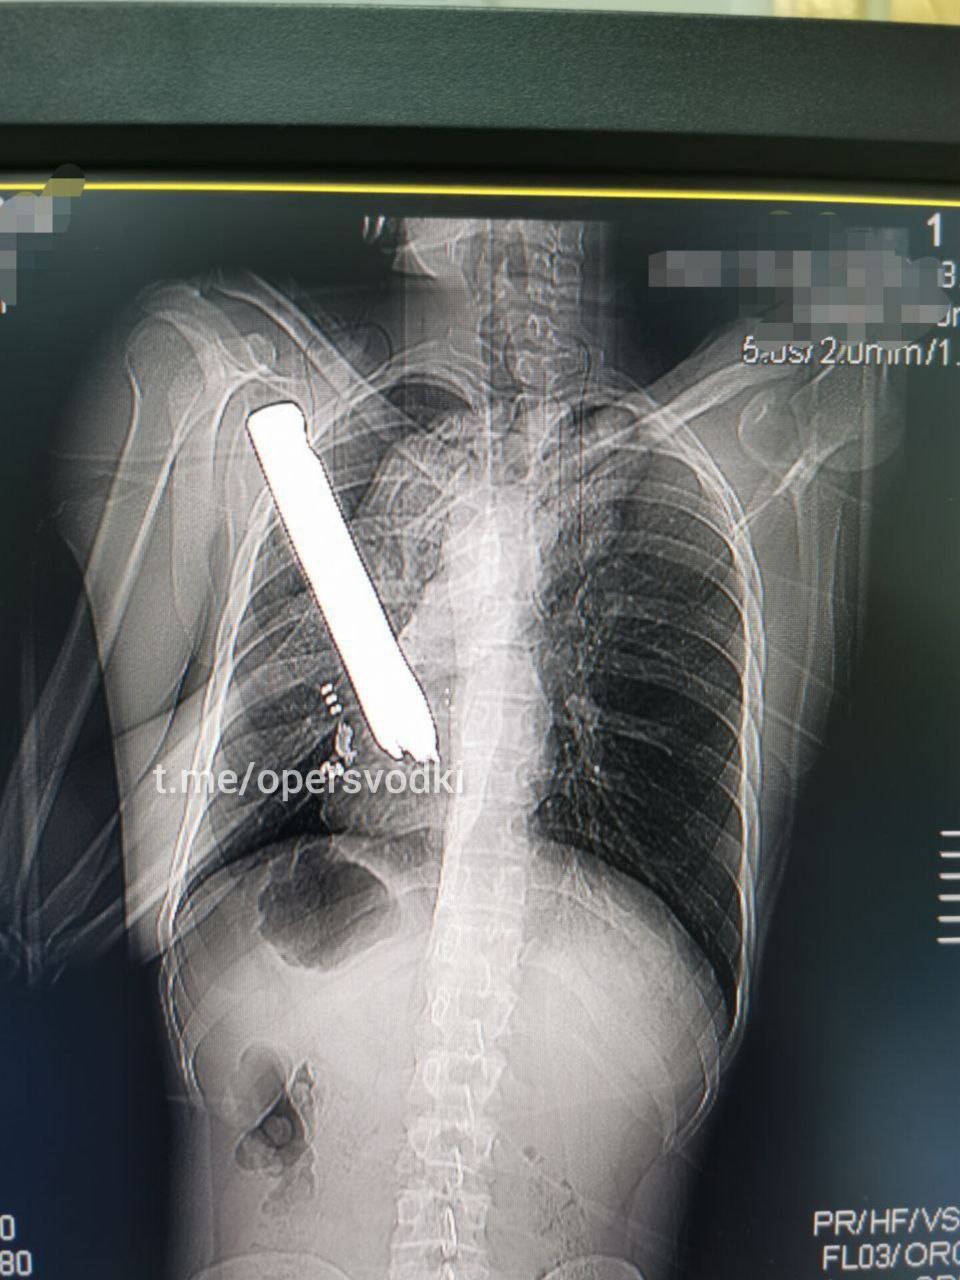

Боец, передвигаясь на бронемашине, наехал на мину. На рентгене определяется инородное тело металлической плотности в груди. Военный хирург грамотно извлёк инородное тело из груди российского бойца. Им оказался каркас от сиденья. Боец прошел лечение, восстановился и уже вернулся в строй.